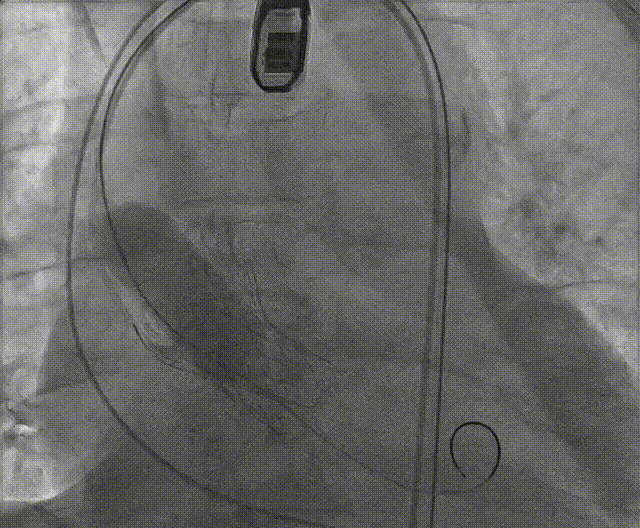

手术流程概括

22球囊扩张,无明显腰增,无造影剂泄露。

瓣膜初始零位释放,释放后位置尚可,决定完全释放。

瓣膜释放后有瓣周漏显示决定进行球囊后扩。

后扩后形态良好,瓣膜展开充分,轻微瓣周漏。